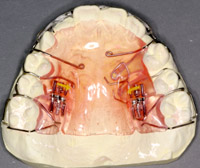

この時期の矯正装置は、ほとんど取りはずせる装置です。一部固定式や頭などにかぶるものもあります。

床矯正装置